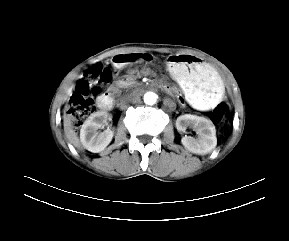

标题: CT19533:病变来源于哪?

患者,男,发现上腹部包块两月余。

病变位于肝胃间隙,实际就是位于小网膜囊(左肝下后间隙),呈轻度不均匀性强化,腹腔内及腹膜后见多发肿大淋巴结。所以我考虑肝胃间隙恶性胃肠间质瘤并淋巴结转移。

病灶强化不显著,灶周及腹膜后见多量淋巴结肿大,考虑淋巴瘤可能,其次考虑间质瘤

病灶与胰腺分界不清,来源于胰腺?

强化后病变与胃壁分界清楚,并且血供不是来源胃壁血管。考虑胰腺颈体癌并腹腔腹膜后淋巴结转移。